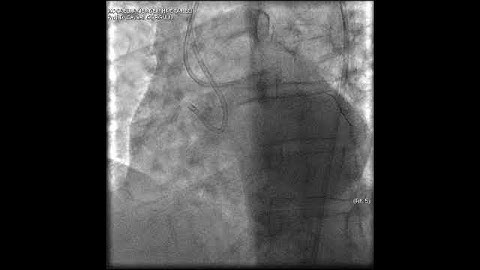

LAD Ostial CTO- Complex PCI with AWE